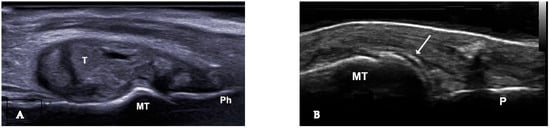

Figure 2.

(A). Urate deposits, grade 3 (definite and severe) visible in longitudinal view at the first metatarsophalangeal joint. (B). Urate deposits at de surface of the metatarsal bone cartilage—double contour sign. MT—metatarsal bone, P—phalanx, T—intraarticular tophus, arrow—double contour sign.